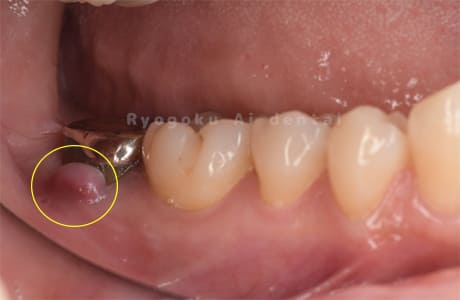

Case08

-

- 原因

- 慢性根尖性歯周炎

- 治療内容

- マイクロエンド

- 治療費用

- 121,000円

左下が腫れているとのことで来院された患者さんです。根の先に病気を作っているため、マイクロスコープを使用した治療を提案し、進めていきました。現在も経過良好です。

<リスク・副作用>

術後は痛み、腫れ、痺れなどの副作用が生じる場合があります。症状が再発する可能性があります。